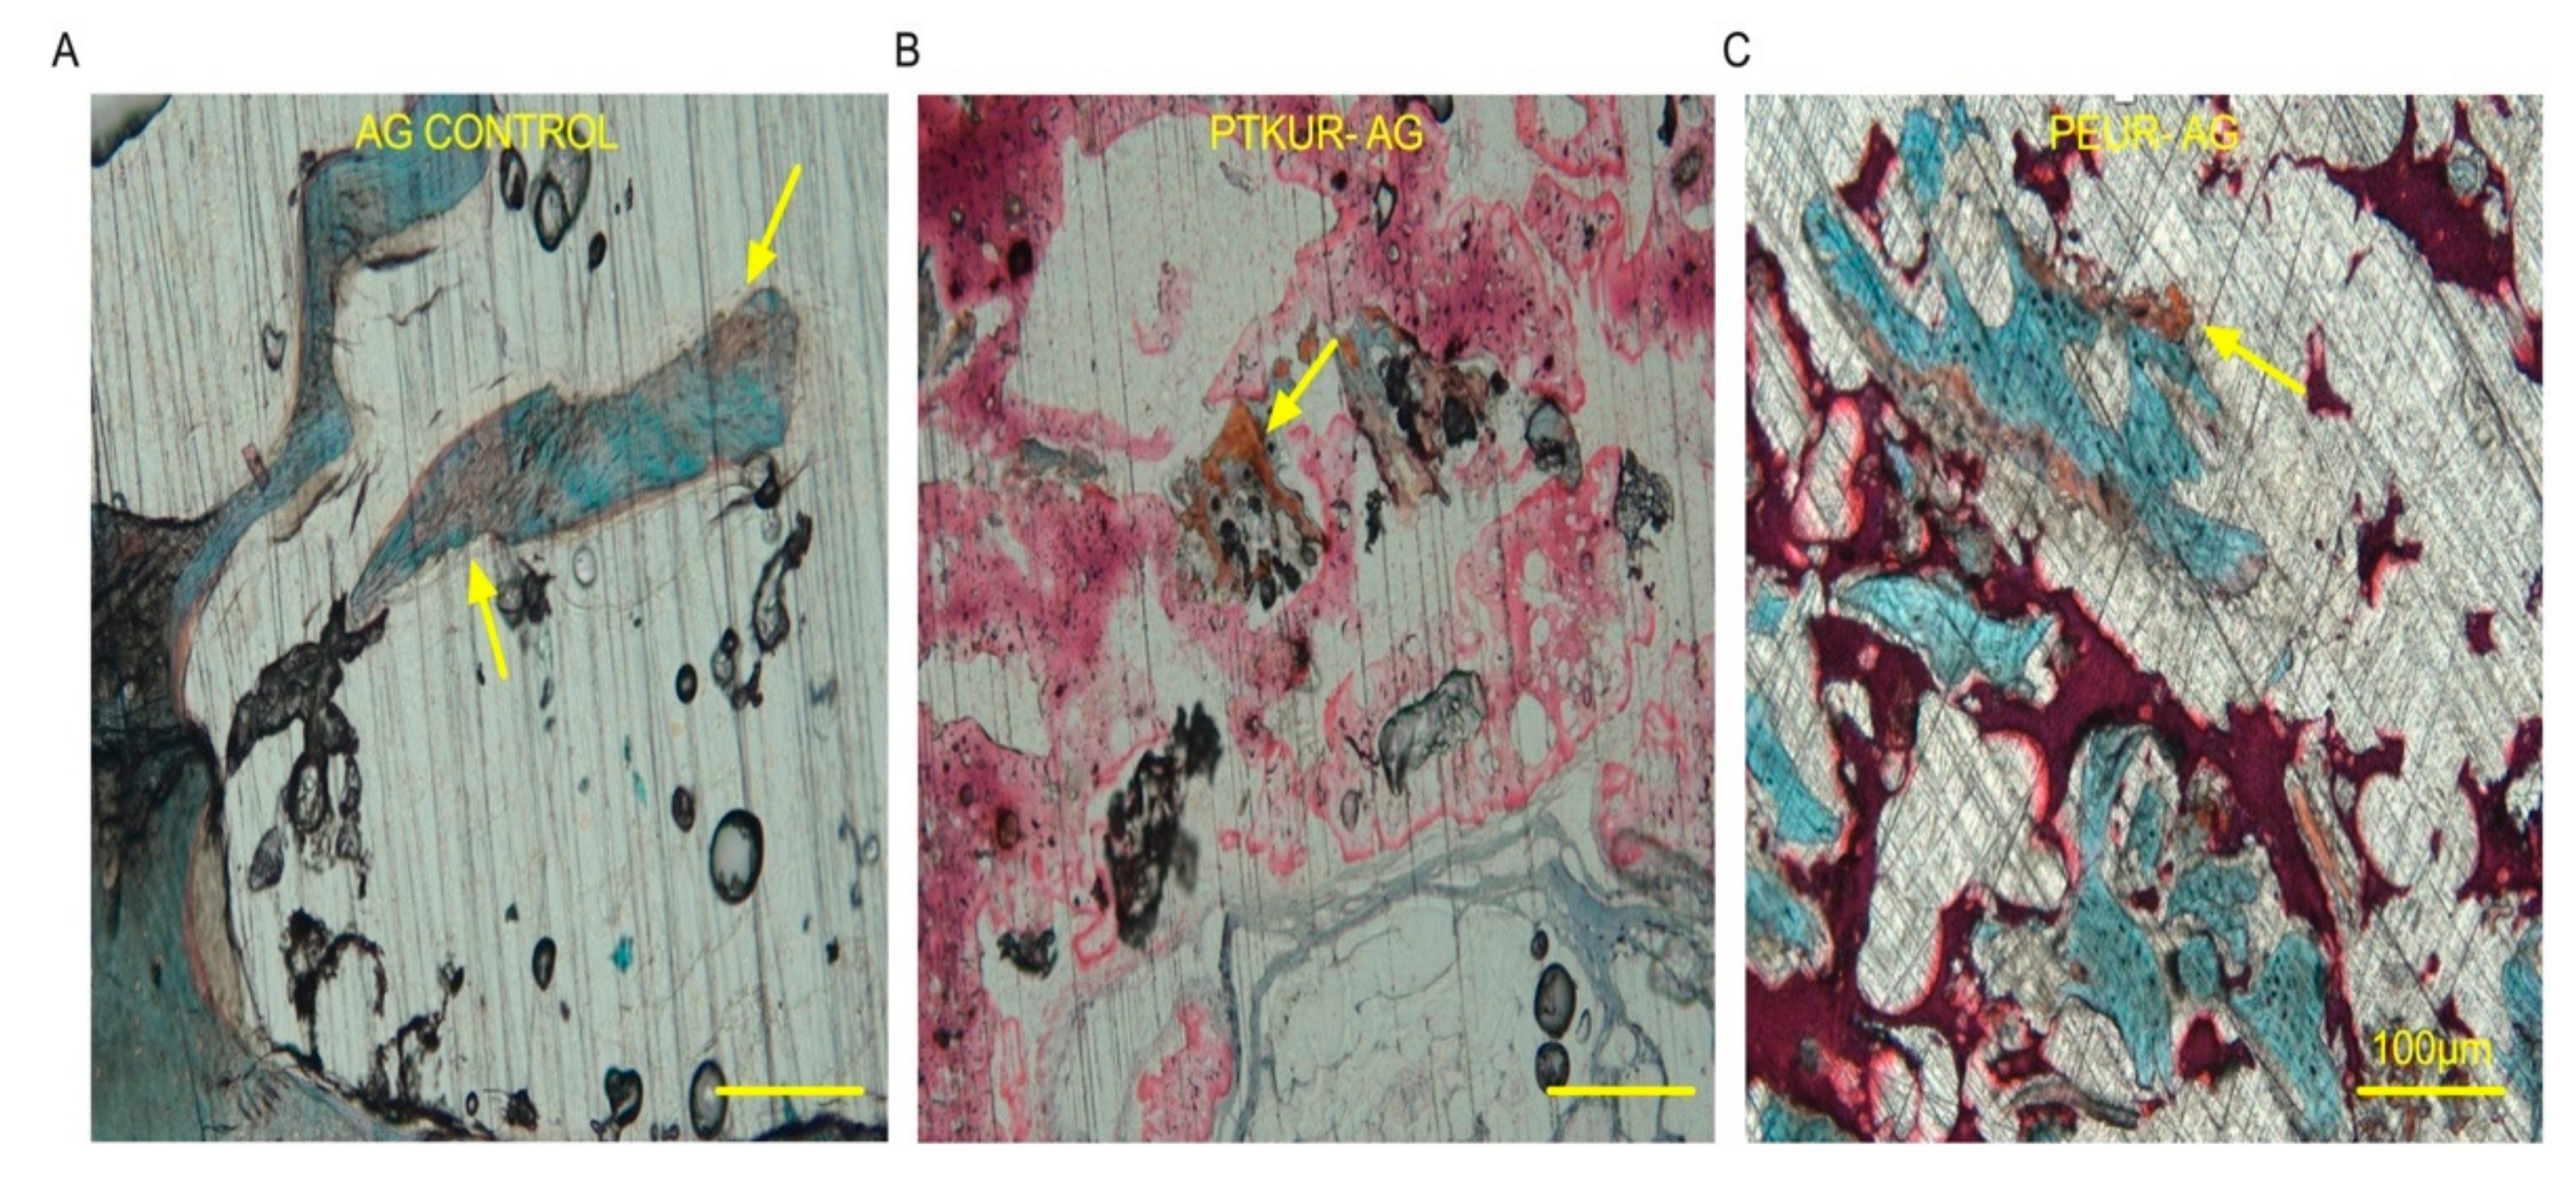

3.3. PTKUR and PEUR Graft Remodeling